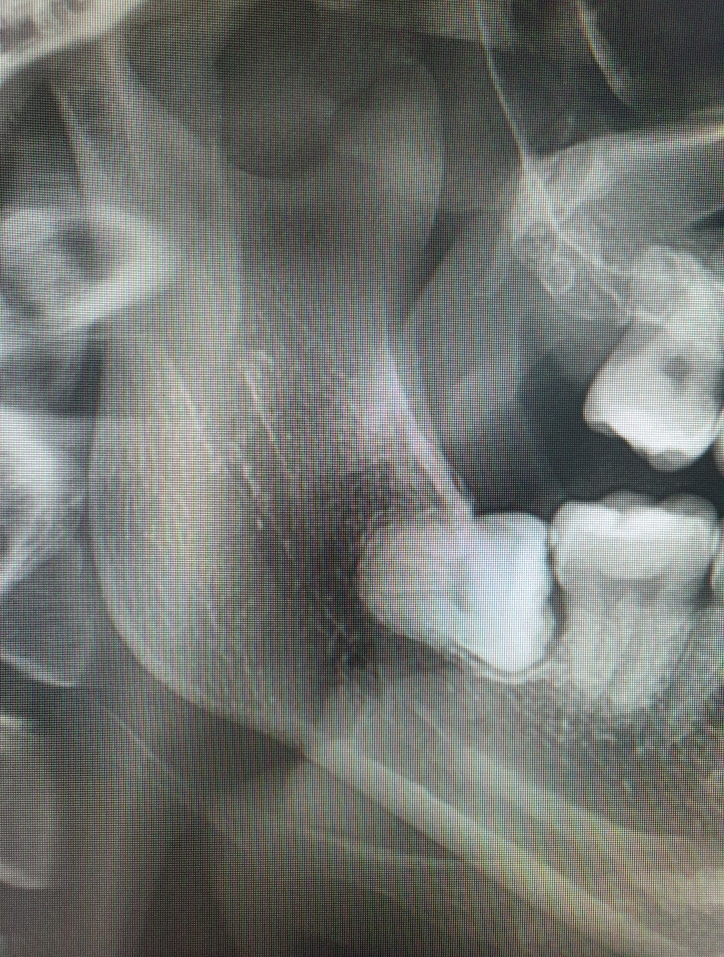

40대 중반의 매복 사랑니 발치

사랑이아프니 구강악안면외과 치과의원 강남점 내가 다니는 치과 원장님이 소개해 주신 사랑니 발치 전문병...